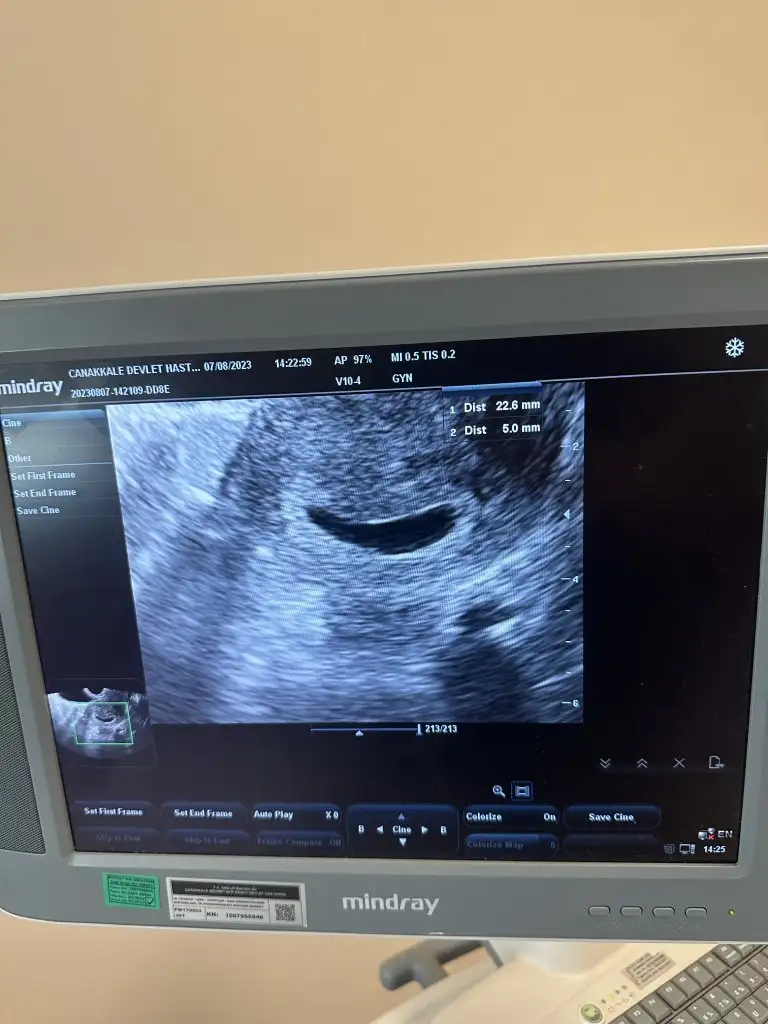

Beş haftalıgız ve pazartesi günü ultrasona gittim. Ve doktorum çok olumsuz konuştu, saglıksız olabilir gibi şeyler söyledi

Kesenin şekli de yuvarlak değil zaten o yüzden mi dedi bilmiyorum… bu tarz yaşayan var mı hiç içinizde ?

Canım sen kalp atışını duydun mu bebeğin? Kesenin şekli gercekten bozuk görünüyor inşallah sıkıntılı değildir.☹️ Beklemek çok zor oluyor gercekten.

Canım duymadım. Hatta sadece kese var yani içinde bebek de yok bir hafta daha bekleyin dedi